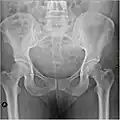

Рентгеновский снимок женского таза в прямой проекции, может использоваться для уточнения размеров таза

Размеры и форма таза имеют важное значение для родового процесса и подлежат измерению и оценке у всех беременных. Для определения внешних размеров таза у живого человека пользуются измерительным инструментом — тазомером Мартина, внутренние размеры выясняются расчётными методами исходя из внешних, также применяется мануальное исследование через влагалище и ультразвуковые исследования. Рентгенологические исследования, в том числе компьютерная томография, у беременных применяются в исключительных случаях для уточнения в виду нежелательного влияния ионизирующего излучения на плод и красный костный мозг женщины[1].